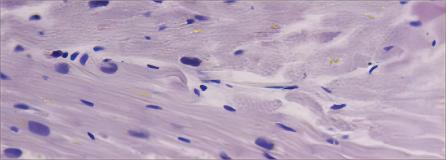

Precision heart section histological assay. (Fischer, 2019)

Precision-cut Heart Slice Model

Precision-cut heart slices, with their combination of intact tissue, functionality, multi-cellularity, and extracellular matrix components, offer an excellent alternative for investigating the contractility and electrophysiology of the heart. They also provide an excellent platform for research related to drug targets, gene function, and cell plasticity in adult myocardium.

1. Fischer, C.; et al. Long-term functional and structural preservation of precision-cut human myocardium under continuous electromechanical stimulation in vitro. Nat Commum. 2019, 10(1): 117. Distributed under Open Access License CC BY 4.0. The original image was modified by keeping part (b).